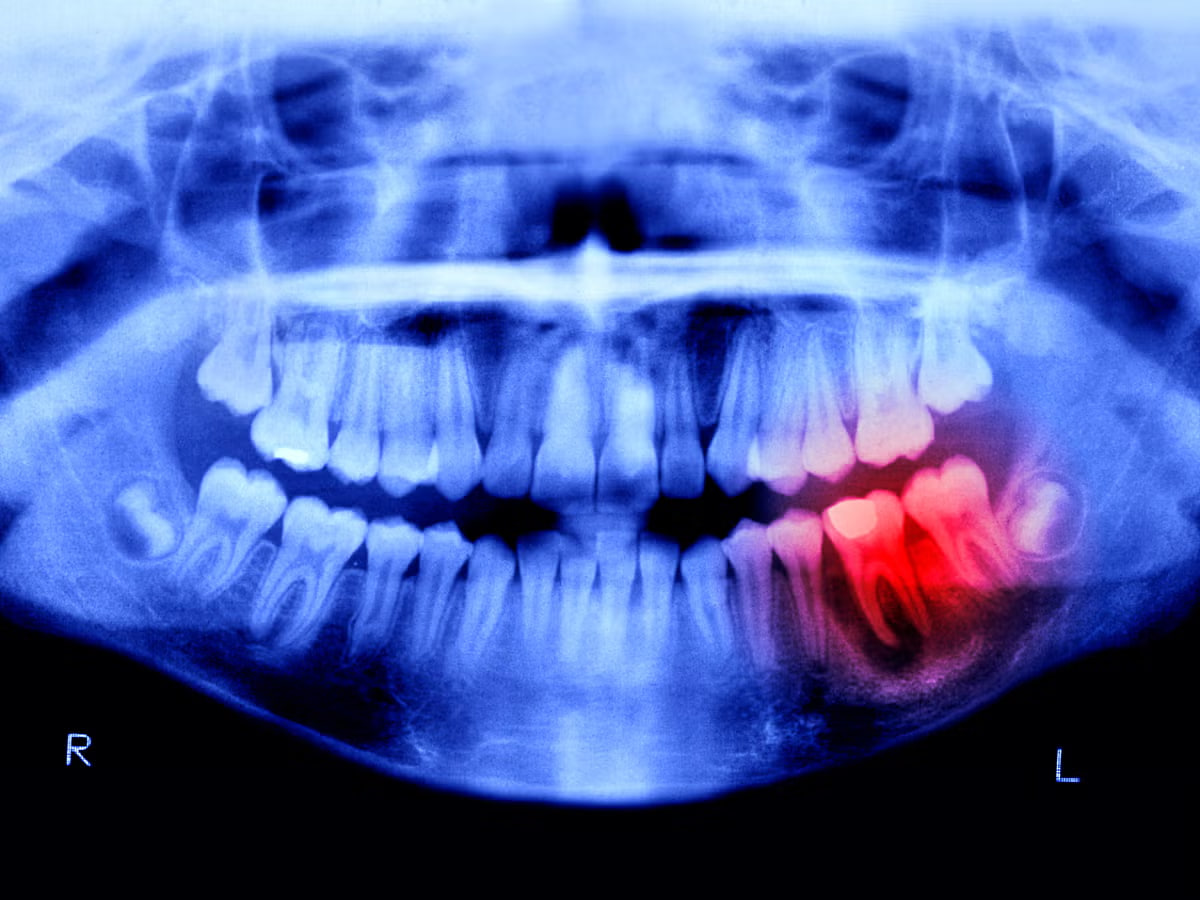

To‘kilgan tishlarni o‘stiruvchi dori 5 yildan keyin chiqishi mumkin

Yaponiyalik olimlar to‘kilib ketgan tishlarni o‘stiruvchi dorining klinik sinovlarini boshladi.

Yaponiyada tish o‘sishini rag‘batlantiruvchi dori vositasining dunyodagi birinchi klinik sinovlari boshlandi. 2024 yilda boshlangan tadqiqotning yangi bosqichida 30 yoshdan 64 yoshgacha bo‘lgan 30 nafar erkak ishtirok etmoqda.

Ishlanma ba’zi sutemizuvchilarda tishlarning o‘sishini to‘xtatuvchi USAG-1 antitanasini ko‘p yillik o‘rganishga asoslangan. Kioto universiteti olimlari uning suyak morfogenetik oqsili (BMP) bilan o‘zaro ta’sirini bloklash usulini topdi, bu esa tish to‘qimalarining tiklanishiga yo‘l ochdi. Usul onkologiyaga qarshi kurashda keng qo‘llaniladigan texnologiya - monoklonal antitanachani qo‘llashga asoslangan.

Yangi dori venaga yuboriladi. Uning xavfsizligi avvalroq hayvonlarda o‘tkazilgan tajribalarda tasdiqlangan.

«USAG‐1 blokirovkasi tishlarning o‘sishiga olib kelishi ma’lum edi. Bu manipulyatsiya to‘liq regeneratsiyaga olib kelishi mumkinligini aniqlash qoldi. Endi biz qo‘limizdan nima kelishini bilamiz», dedi Katsu Takahashi, Kitano shifoxonasining stomatologiya va yuz-jag‘ jarrohligi bo‘limi mudiri.

Agar klinik sinovlar muvaffaqiyatli o‘tsa, 2026 yilda olimlar tug‘ma adentiya - to‘rt va undan ortiq tish yo‘qligi bo‘lgan bolalarni davolashni boshlashni rejalashtirmoqda. Pirovard maqsad - 2030 yilgacha hammabop dori vositasini ishlab chiqarish.